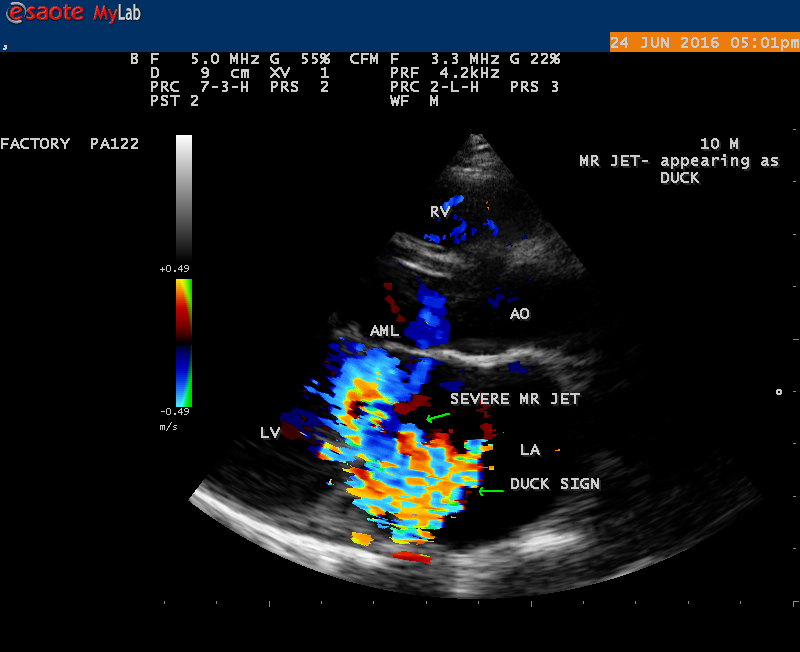

Echocardiography is the only noninvasive method available for direct visualization of endocarditis-induced lesions. Echocardiographic finding in patients with infective endocarditis was initially observed by Dillon [25] and Spangler, et al [26]. The vegetation will grow in size, either as a sessile clump or a highly mobile and even pedunculated mass with the potential for embolization. Vegetation can be detected when the valve attached mass reach a diameter of ≥ 2 to 3 mm [27]. In both children and adults, 2-D echocardiography is usually the more sensitive technique with sensitivity in children up to 80% [28]. Valvular dysfunction due to tissue disruption or large obstructing vegetation can be visualized and quantitated by echocardiogram with Doppler [29]. The detection of a large eccentric jet adhering, swirling, and reaching the posterior wall of the LA is in favour of significant MR (mitral regurgitation) as shown in Figures 22, 24 and 25.

The most common and direct evidence of infective endocarditis is the vegetation and it begins as a microscopic focus of infection and gradually grows into a conspicuous mass. It is typically an irregularly shaped, highly mobile, echogenic mass attached to the free edge of a valve leaflet ( most commonly at the coaptation line) and tends to develop on the ‘upstream’ side of the valve leaflets ( ie, the ventricular side of aortic valve and the atrial side of mitral and tricuspid valves. They may be seesile or pedunculated, but usually has an oscillating or fluttering motion, a typical feature of most vegetations. Vegetation move with the leaflet in a more chaotic (‘oscillating’) manner and it may prolapse through the valve into the LV (left ventricle) as it opens as shown in Figures 3, 4 and 16 and into LA (left atrium) as it closing (Figure 5 and 6) . The mass of vegetation is typically homogeneous with echogenicity similar to that of the myocardium. The infectious process often alter the valvular structure and function. Extensive involvement of the leaflet may result in chordal rupture, leading to severe regurgitation as shown in Figure 21 . Direct and typical signs of RMCT (ruptured mitral chordate tendineae) were chain-flail or whiplash-like changes and had an incidence of 86.7%, causing severe regurgitation and mitral chordal rupture is the leading cause of flail mitral leaflet[30]. A large vegetation may obstruct the valve orifice as shown in Figure 1 and 2 , sometimes termed as “obstructive-type bacterial endocarditis” and producing a functional valve stenosis ( Ping-Pong mitral stenosis [31]) similar to left atrial myxoma as shown in Figure 29.

The shape and size of vegetation are quite variable and mostly it is polypoid [32]. The typical vegetation is a ‘sessile’ or ‘ pedunculating’ valve – attached mass. A ‘sessile’ vegetation had to be completely attached to the valve as shown in Figures 34 and 35 in a 63- year old male, in which a large vegetation is attached to the atrial side of anterior mitral leaflet [33-Figure 13.3-A], producing severe mitral regurgitation as shown in Figure 36 and a mobile vegetation showed a pedunculating part prolapsing into the ventricle as shown in Figure 3 and 4 or atrium as shown in Figure 5 [33-Figure 13.1] in a 10-year old female child. A vegetation was considered as ‘definite’ when shaggy echoes in the M-mode study as shown in Figure 20 . and a corresponding mass without restricted valve motion in the two-dimensional echocardiogram were found as shown in Figure 16 and 30 [33-Figure 13.7]. The vegetation vary in size, often being just a few mm and sometimes reaching to 2-3 cm. A vegetation must be atleast 3 to 6 mm in size to be reliably seen. The mean size of vegetation was 0.6 mm (range 3 to 28) and vegetation > 10 mm in diameter was defined as ‘large’ and those ≤ 10 mm in diameter was defined as ‘small’ and ≥ 15 mm is ‘very large’. Vegetations resulting from fungal infections (candida, aspergillus) are usually much bigger than bacterial vegetations and can be so big to be mistaken for a cardiac tumor. The large vegetations are at increased risk for embolic complications [34], especially on the anterior leaflet of the mitral valve with mobility [35]. A vegetation size of 3.2 x 4.4 cm is called as ‘giant vegetation’ on the mitral valve with a fibrillary appearance of the mass [36- Figure 3] as shown in Figure 1 is an important predictor of embolic phenomena in patients with infective endocarditis causing severe mitral regurgitation as ‘Duck’ shaped jets (Figures 24 and 25 ), disorganized (Figure 21) and sometimes the regurigitant jet splits into two components as one into LA and the second one into LV simultaneously as a bileaflet jets (Figure 10 ) similar to bileaflet structure of AML with vegetation masses (Figure 9 ) . The size of the largest vegetation reported on the mitral valve in the literature in patients with bacterial endocarditis is 7x4 cm[37]. In a study of Nunes, et al[38], vegetation size >13 mm was the only independent predictor of mortality, but some studies [39],[40] did not had an increased embolic risk in patients with vegetation focused only on its presence and size and not on their location. Embolic complications may occur in infective endocarditis(20.6%)and were not more prevalent in the groups with large vegetations [41]. However, Wong, et al [42] found an increased need for surgery in patients with a large vegetation (>10 mm).

The shape of vegetation varies in this child as ‘popcorn’ like (Figures 1,3 and 4 ), rod-shaped (Figure ), basket shaped (Figure 7 )[33-Figure 13.3], ‘baby in hand’ appearance (Figure 18), ‘cucumber shaped (Figure 2 ) and a ‘bunch of plantain’appearance (Figure 33 ), ring shaped (Figure 19 }, bileaflet structure (Figure 9 )with bileaflet MR jet as shown in Figure 10 . and kissing forms (Figure 13 - parasternal long axis view, Figure 14 - apical four chamber view and Figure 15 - short axis view)

The anatomic disruption of a portion of the mitral valve apparatus dueto the underlying rheumatic valvulitis with predisposing infective endocarditis which form a vegetation , resulting an eccentric regurgitation jet with orientation opposite in direction of the leaflet having the anatomic defect such as ‘flail’. In the presence of ‘flail leaflet’, the mitral regurgitant spectral signal may have an atypical appearance and the flail portion oscillate in the spectral signal of regurgitant flow stream to produce a ‘tiger stripe’ appearance as shown in Figure 27. associated with ‘whistling’ sound on auscultation[33-Figure 11.85]. The mitral regurgitation (flail MR) jet is chaotic as shown in Figure 26, highly eccentric (Figure 22) and disorganized with one component behind the anterior mitral leaflet and the second component directed towards posterior immediately as in Figure 21 [33- Figure 11.79].

The severity of eccentric MR is underestimated because of coanda effect. If the regurgitant jet area fills < 20> 40% indicate severe regurgitation. The vena contracta ( the neck or narrowest portion of the jet), typically imaged perpendicular to the commissural line in parasternal long axis and apical four chamber views is well defined in both central and eccentric jets, but not in chaotic, disorganized jets due to flail leaflets. Its width < 3> 7 mm defines severe MR and a mean value of > 8mm indicates severe functional MR. The flow convergence method based on PISA (proximal isovelocity surface area) may not applicant for eccentric and multiple jets or complex and elliptical regurgitant orifices to assess the severity of mitral regurgitation.. The adaptation of LV to the increased volume overload is reflected by LV dimensions and ejection fraction.. In chronic compensated phase, the forward stoke volume is maintained through an increase in LV ejection fraction >65% and the patient could be asymptomatic. In chronic decompensated phase of MR, the forward stroke volume decreases and the LA pressure increase significantly. The patient may be still asymptomatic and the LV ejection fraction may be in the low normal range despite the presence of significant muscle dysfunction. The contractile function decreases silently and become irreversible. In the current guidelines, surgery is recommended in asymptomatic patients with severe organic MR when the LV ejection fraction is ≤ 60%. However, in acute stage, the LV ejection fraction increases in response to the increased preload. The end-systolic diameter is less preload dependent than the ejection fraction and it may be more appropriate to monitor the global LV function. The end-systolic diameter > 45 mm also indicate the need for mitral valve surgery [43]. In this child, the LVESD (end-systolic diameter) is 30.7 mm and the ejection fraction (EF) is 66% as shown in Figure 19. New parameters are currently available for a better assessment of LV function. A systolic tissue Doppler velocity measured at the lateral annulus <10>40-50mm) may predict the onset of atrial fibrillation and poor prognosis in patients with organic MR[48]. The excess regurgitant blood entering in the LA may induce acutely or chronically a progressive rise in pulmonary pressure and the presence of TR (tricuspid regurgitation) as shown in Figures 26 and 28 permits the estimate of systolic pulmonary arterial pressure and mitral valve surgery is recommended when it is > 50 mmHg at rest and LA reverse remodeling may occur after surgery. The severe TR may cause a decrease in hepatic vein systolic velocity and systolic flow reversal may occur as shown in Figure 32 and its sensitivity is 80% [49]. The TR (tricuspid regurgitation) jet velocity in this child is 4.03 m/s as shown in Figure 28 which corresponds to a systolic pulmonary artery pressure of 65 mmHg.